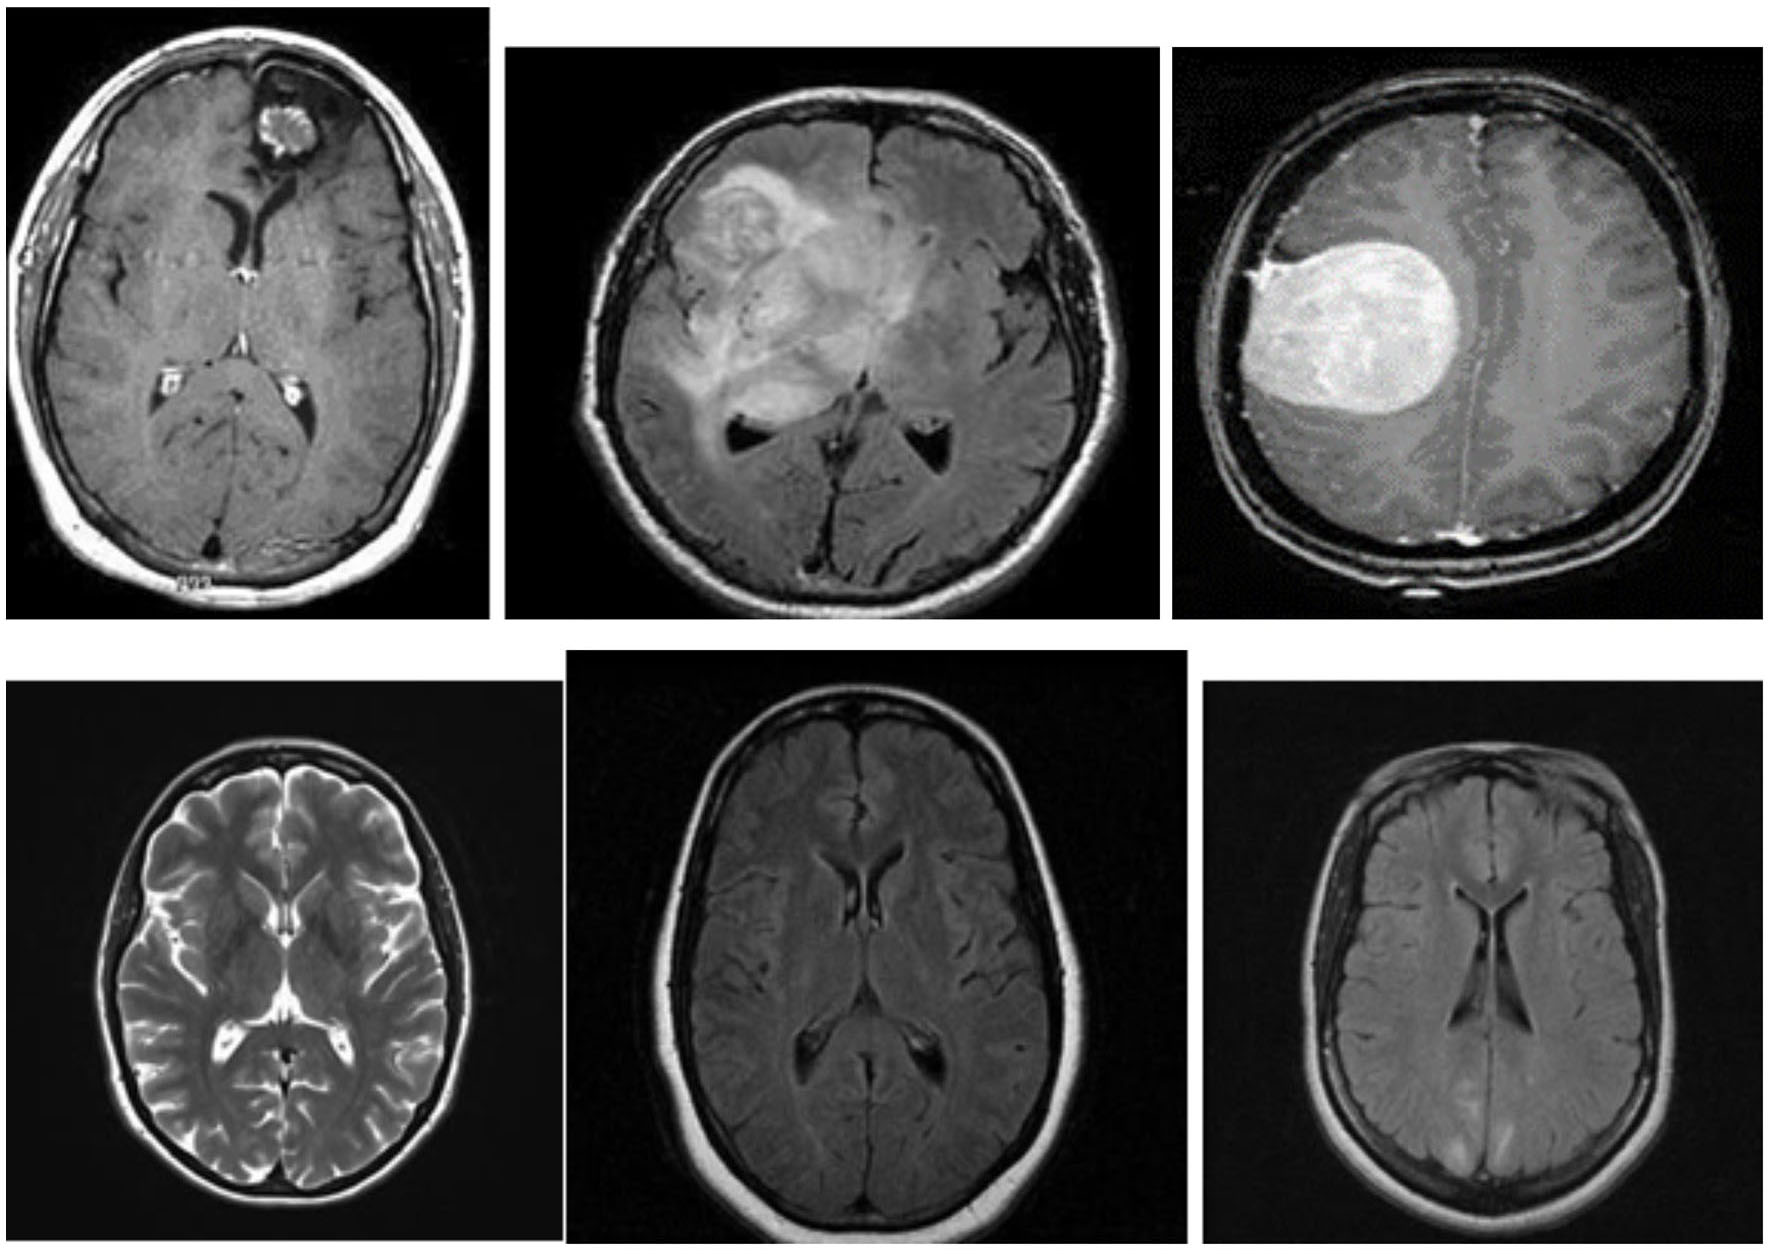

Figure 3 shows examples of MR images of the dataset with and without malignancies. The black frames surrounding the images in the dataset have varying sizes. Pre-processing was performed to normalize the images before training.

Figure 3

MR images with and without tumor from the dataset.